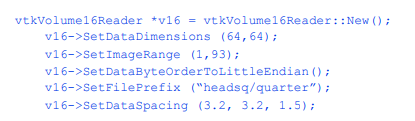

VTK提供了几种图像读取器,包括一个可以读取上述类型的原始格式的vtkVolume16Reader。为了读取这些数据,我们实例化类并设置适当的实例变量,如下所示。

FilePrefix和FilePattern实例变量一起工作,生成一系列片中的文件名。fileppattern—默认为%s。%d -通过对FilePrefix执行c语言sprintf()生成要读取的文件名,并将当前文件号写入FilePattern格式说明符。